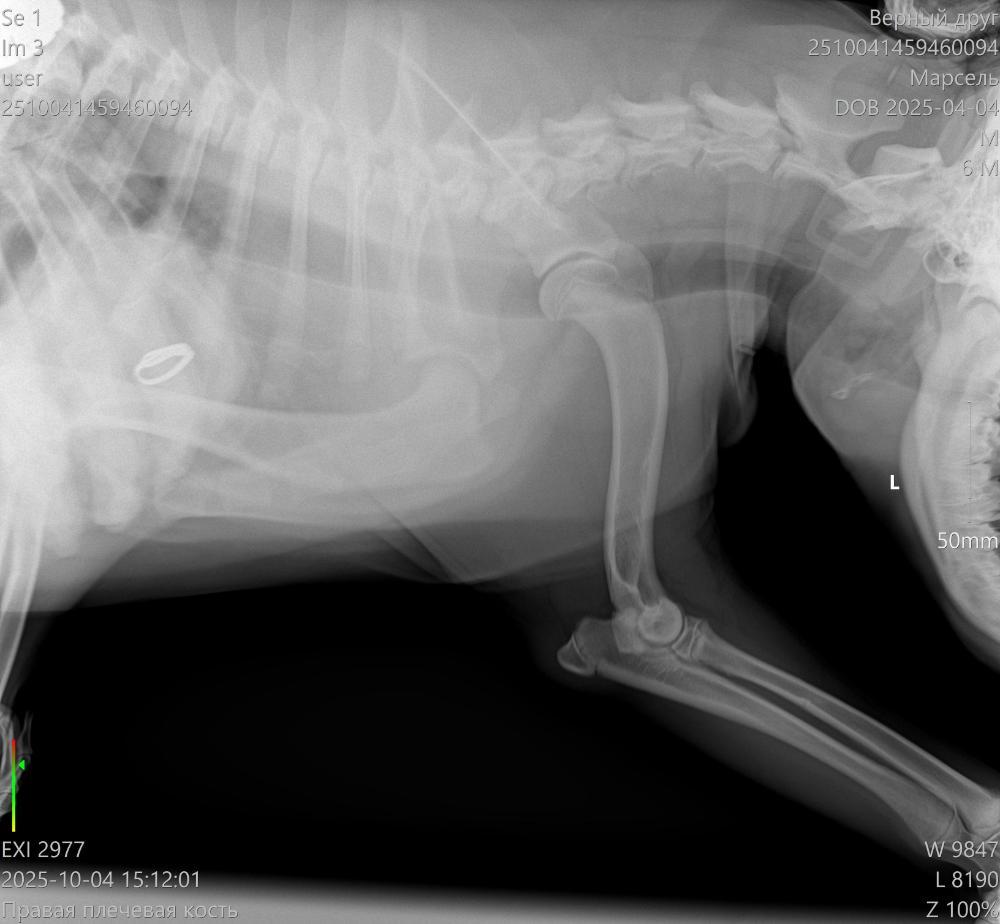

Здравствуйте. Щенок 6,5 месяцев начал периодически хромать на правую лапу. Сначала думали, что может ушиб или потянул лапу, съездили в клинику, нас отправили к ортопеду. Сходили к нему и сделали ренген и КТ. По результатам КТ: "Заключение: 1. Признаки РОХа (расслаивающий остеохондрит) в структуре медиальных надмыщелков плечевых костей обоих локтевых суставов (в правом локтевом суставе выражено в большей степени)."

После КТ были у 2 ортопедов. Один говорит, что нужно срочно делать операцию, второй выписал таблетки и сказал понаблюдать пару месяцев. Подскажите, пожалуйста, может кто-то сталкивался с таким заболеванием? Что лучше - подождать и понаблюдать или делать операцию? Если ждать, то не упустим ли время, а если делать операцию, то щенок еще растет, как это скажется на растущем организме?

2510041459460094_Марсель__04-10-2025 15_07_13_1-1.jpg